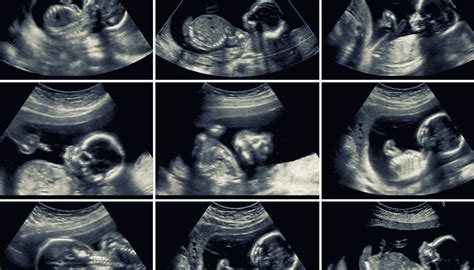

- Ultrazvukové vyšetrenie: Najčastejšie a spoľahlivé určenie pohlavia sa vykonáva pomocou ultrazvuku, zvyčajne okolo 18. - 22. týždňa tehotenstva, kedy sú vonkajšie pohlavné orgány dostatočne vyvinuté na vizuálnu identifikáciu.

- 18. - 22. týždeň: Možnosť spoľahlivého určenia pohlavia na ultrazvuku, prvé vnímateľné pohyby plodu.